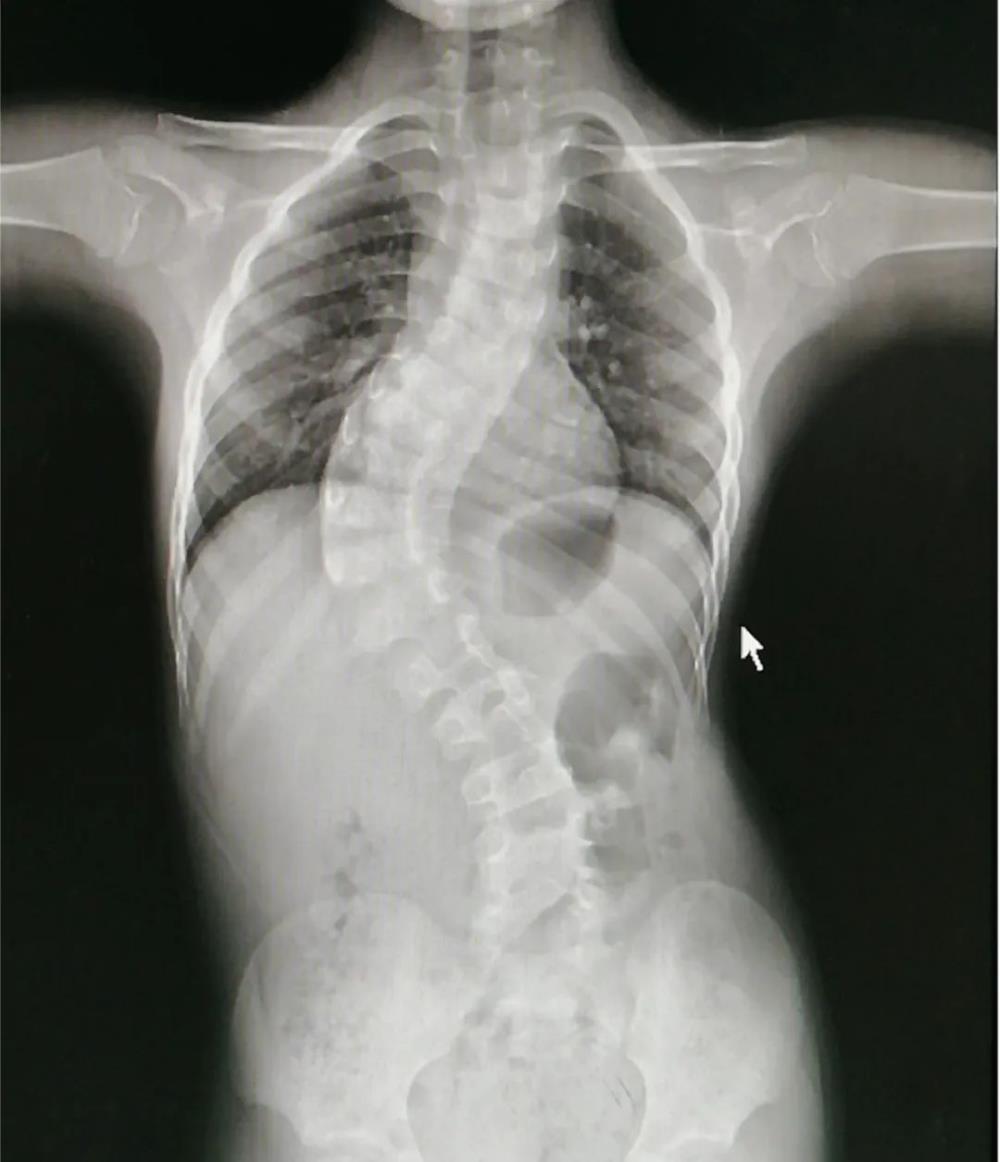

一、什么是脊柱侧弯? 脊柱侧弯:又称脊柱侧凸,它是一种脊柱的三维畸形,包括矢状位、冠状位和轴位的序列异常。如果正位全脊柱X线片显示cobb角大于10°的侧方弯曲,即可诊断。

三、脊柱侧弯治疗原则1、 早发现、早诊断、早干预、早治疗一越早越好;2、 不同类型、不同年龄阶段的治疗原则完全不同;3、 一旦发现,必须咨询专业的脊柱外科医师;4、 根据Cobb角大小选择不同治疗方法: 当Cobb角大于40°,可选择手术治疗 当Cobb角小于40°大于20°,可矫形器治疗配合物理治疗、矫正体操。 当Cobb角小于20°,可物理治疗及矫正体操。 当Cobb角小于10°,观察,并定期复查。 标准化的阶梯治疗流程